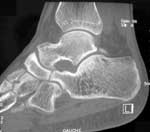

Imagerie par CT-scan

Depuis le début des années 80, l’imagerie par tomographie computée a pris une place centrale dans le diagnostic des synostoses du tarse.

A l’inverse, dans les barres TC ou multiples, cette technique est d’un apport essentiel dans le diagnostic et la caractérisation (type, localisation et étendue) de la lésion.

Les critères de diagnostic sont le plus souvent ceux cités par KUMAR (Tableau 3). On y ajoutera l’hypertrophie du sustentaculum et l’inclinaison médio-caudale de la facette moyenne déjà mentionnés plus haut (23,68). Le diagnostic des types I et II pose rarement des problèmes (31,68,42,69)(Fig. 14, 15, 16).

La difficulté concerne les types III où les modifications sont parfois subtiles et d’interprétation délicate, d’autant plus si l’atteinte est bilatérale (31,68,42).

L’imagerie par CT-scan est donc d’un apport essentiel dans le diagnostic et le traitement des synostoses TC. Elle a remplacé l’incidence de HARRIS et BEATH dans cette indication. Elle reste cependant difficile d’interprétation dans certaines formes, ce qui peut justifier le recours à l’IRM ou à la scintigraphie.